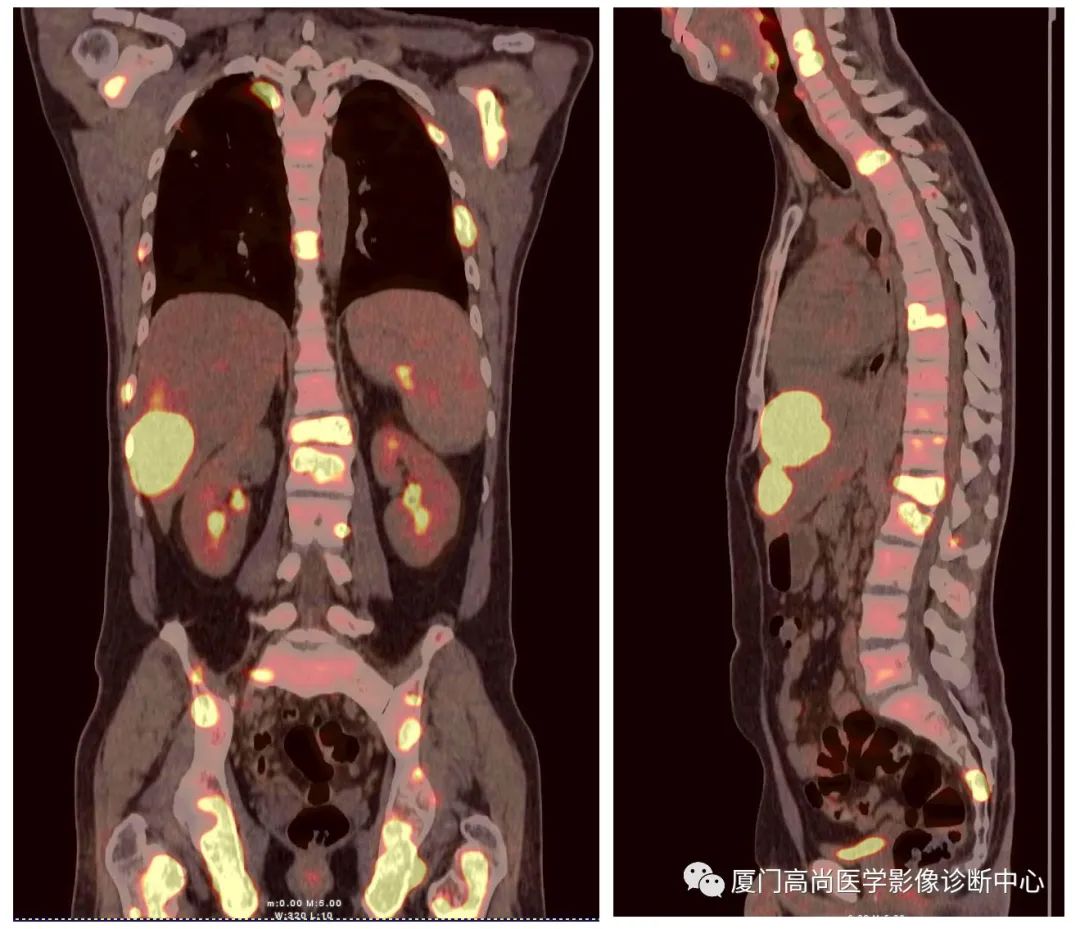

病例1:某男士,36歲,半年前摔傷,當(dāng)時(shí)無大礙,近幾個(gè)月來腰腿痛,并逐漸加重,消瘦10多斤。MRI檢查發(fā)現(xiàn)腰椎、骨盆 骨質(zhì)異常信號(hào),查血各項(xiàng)腫瘤標(biāo)記物正常,因診斷不清而來做PET/CT檢查

淋巴瘤在骨骼、肝臟、脾臟、淋巴結(jié)表現(xiàn)

肝臟、脾臟、骨骼淋巴瘤病灶

骨骼、腋窩淋巴結(jié)病灶

PET/CT發(fā)現(xiàn) :全身多發(fā)淋巴結(jié)腫大,F(xiàn)DG攝取增高;肝臟、脾臟多發(fā)低密度結(jié)節(jié), FDG攝取增高;雙側(cè)扁桃體腫大,F(xiàn)DG攝取增高;全身多處骨骼破壞,F(xiàn)GD攝取增高;上述考慮為淋巴瘤

經(jīng)淋巴結(jié)穿刺活檢 :病理診斷為彌漫大B細(xì)胞淋巴瘤